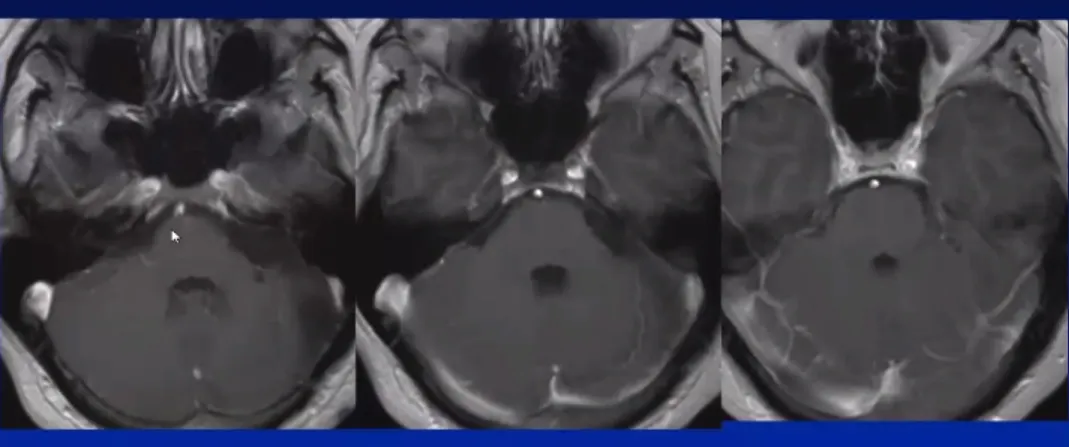

卢卡术前影像

36岁的卢卡,怎么也想不到持续的耳鸣和逐渐下降的听力背后,藏着一个“潜伏”的肿瘤——超过3cm的巨大听神经瘤。

幸运的是,卢卡最终在国际知名神经外科教授的操刀下顺利完成手术,肿瘤被完整切除,术后没有出现面瘫等并发症。十年过去,他回归正常生活,随访一切稳定。

术中全切,术后无面瘫

术后10年随访,一切正常